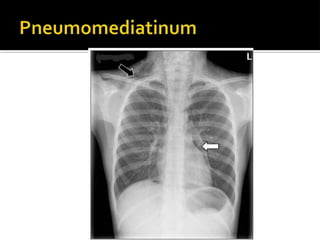

Chest CT

◾ left-sided hydropneumothorax

◾ pneumomediastinum

◾ esophageal thickening